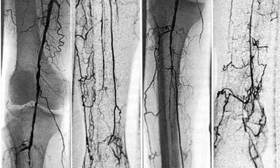

El diagnóstico de la AOMI (Arteriopatía Obliterante de Miembros Inferiores) se basa en el exámen clínico y en las imágenes vasculares, estas imágenes se obtienen a través de un estudio Arteriográfico de los miembros afectados, por medio del uso de Rayos X y medio de contraste.

La Arteriografía de Miembros, permite el estudio ya sea de los miembros superiores ó inferiores, pudiéndose detectar a través de ella, Coagulopatías, Isquemias Agudas por trombos, Estenosis, etc.